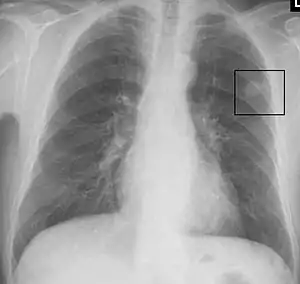

Several NDT methods are related to clinical procedures, such as radiography, ultrasonic testing, and visual testing. Technological improvements or upgrades in these NDT methods have migrated over from medical equipment advances, including digital radiography (DR), phased array ultrasonic testing (PAUT), and endoscopy (borescope or assisted visual inspection).